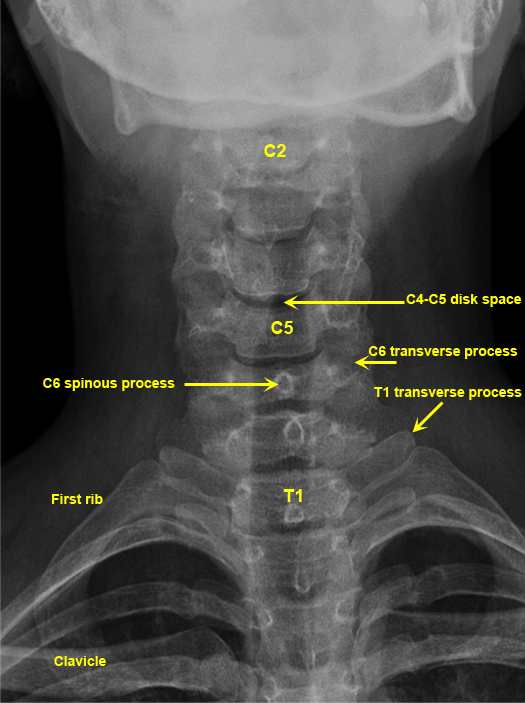

Plain Films of Skull and Spine